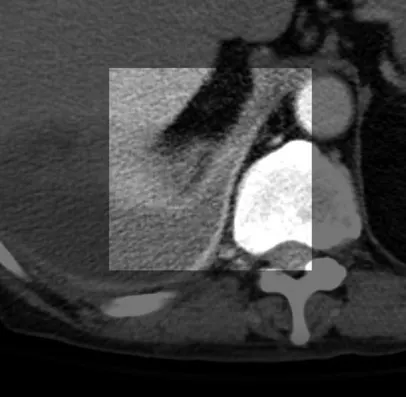

(2) CT 상 Empyema 와 Lung abscess 감별하기

인접한 Bronchi와 혈관들과의 관계

abscess는 갑자기 Bronchovascular 구조물을 interrupt한다.

empyema는 대개 인접한 폐를 변형 시키거나 압박한다

empyema 는 visceral과 parietal pleura를 두껍게 만들면서 서로 분리시킨다

abscess는 두껍고 불규칙한 wall

empyema는 대개 매끈한 walls

pleural enhancement

empyema는 pleurar 가 enhance되는 경향

extrapleural fat

empyema는 extrapleural fat의 부종과 haziness를 보이는 경향